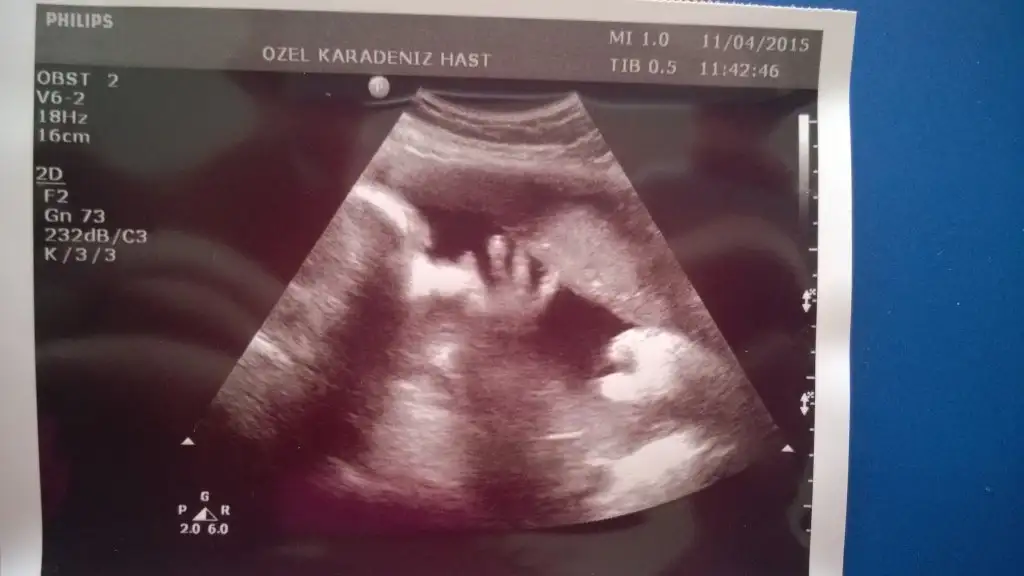

Bugun de raporum bitti tekrar cikip alacagm hemde bebisi gormus olurum.